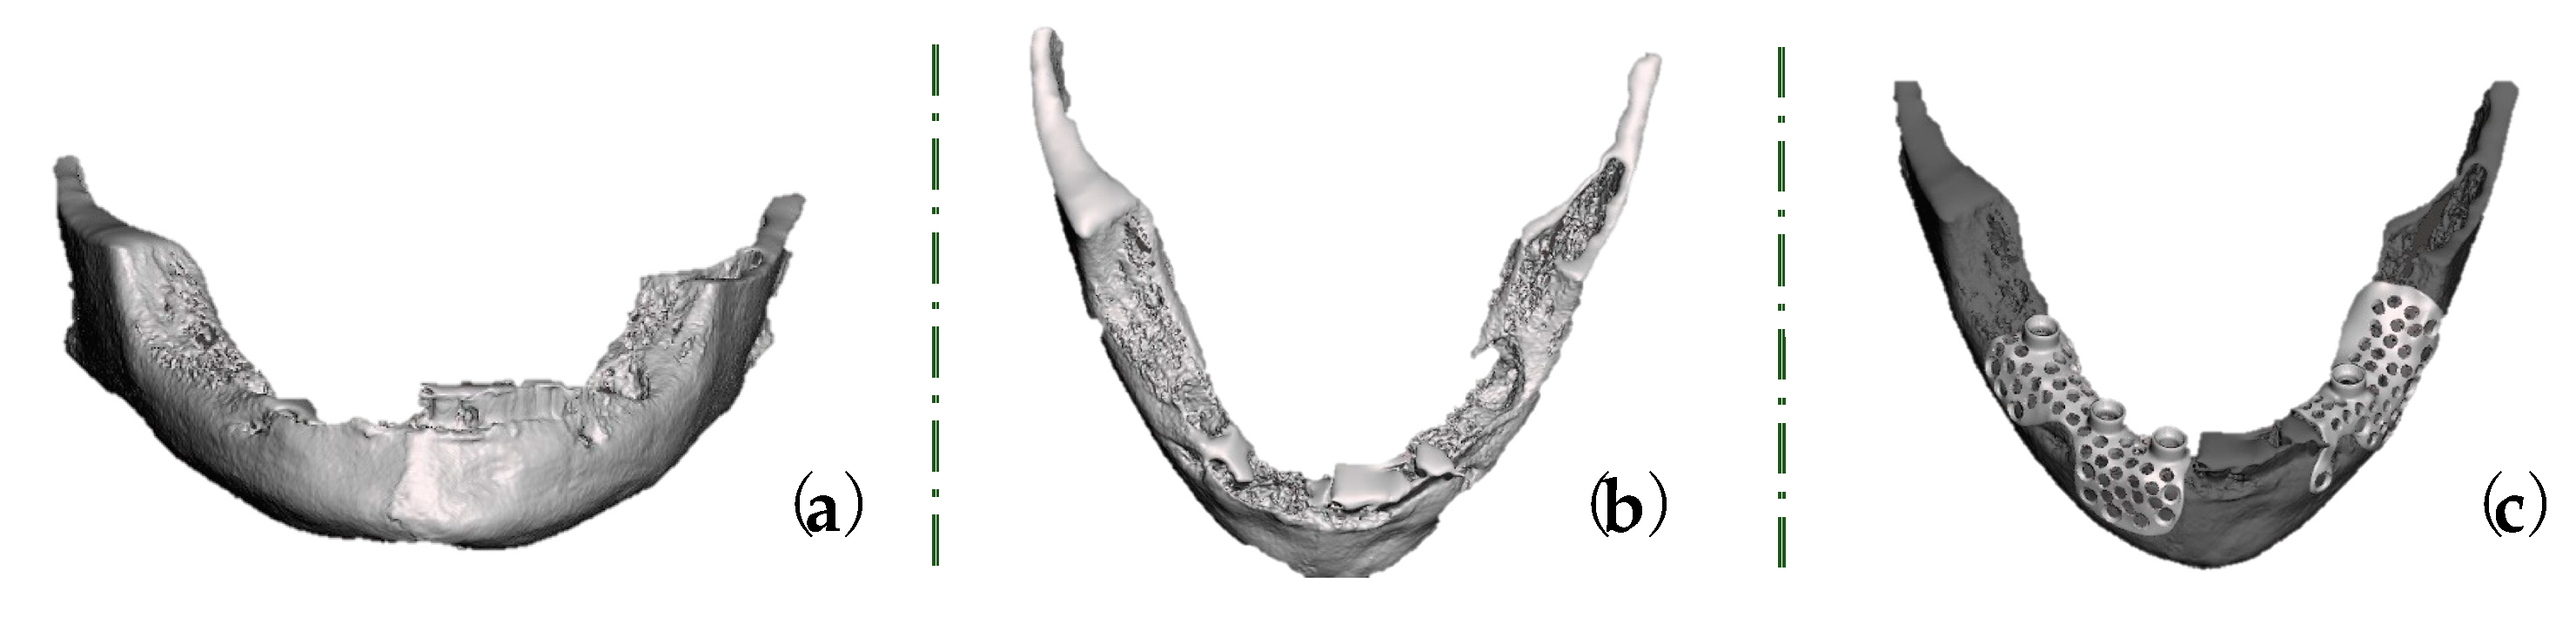

2. Case Report